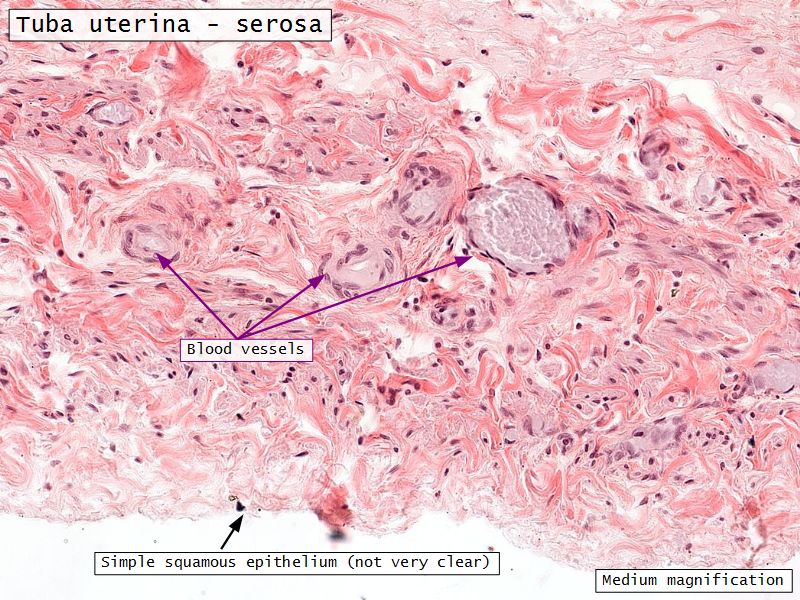

Serosa

- Simple squamous epithelium

- Contains

- Blood vessels

- Lymphatics

- Nerves